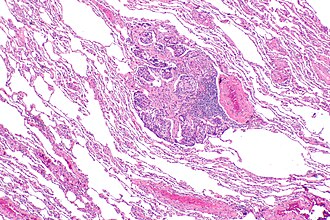

A carcinoid tumourlet; if it were larger it would be a carcinoid lung tumour. H&E stain.

Pulmonary carcinoid tumourlet <5 mm[4][5] Typical carcinoid lung tumour Typical carcinoid lung tumour not a cancer